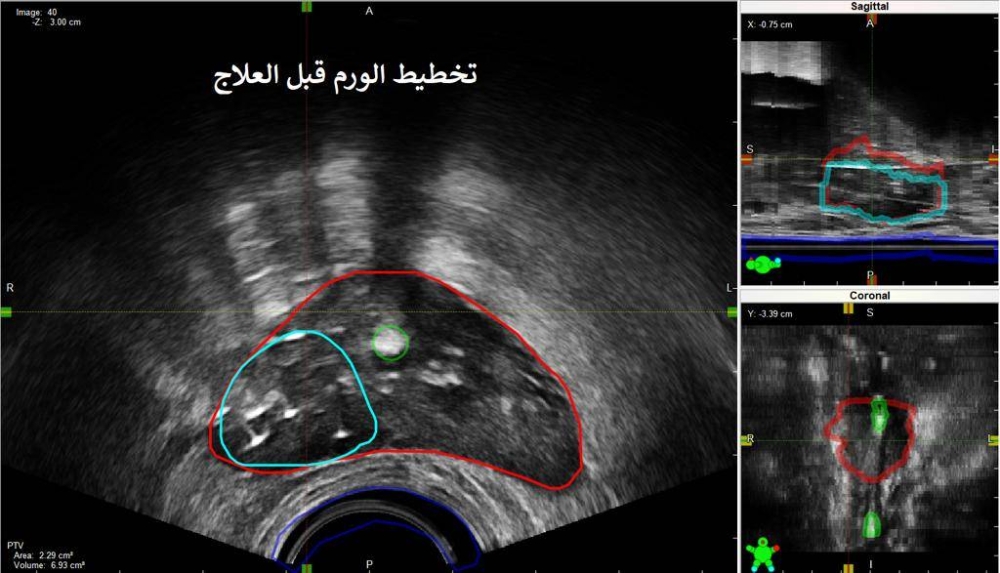

وأضاف أنه منذ عام تبين بعد المتابعة عن طريق فحوصات الدم والأشعة المقطعية والنووية الصبغية وجود ورم رجعي موضعي بحجم 2 سم داخل البروستات؛ وبعد مناقشة الخيارات العلاجية تقرر استخدام العلاج الموضعي "براكي ثيربي" الجزئي .

وفي تفاصيل الإجراء قال د. الرشيدي: "بعد التخدير الموضعي يتم زرع الإبر الجراحية داخل الورم باستخدام أجهزة متقدمة موجهة بالأشعة الصوتية ومن ثم إيصال الجرعة العلاجية الكافية للتخلص من الورم؛ وبإمكان المريض الخروج من المستشفى بنفس اليوم".